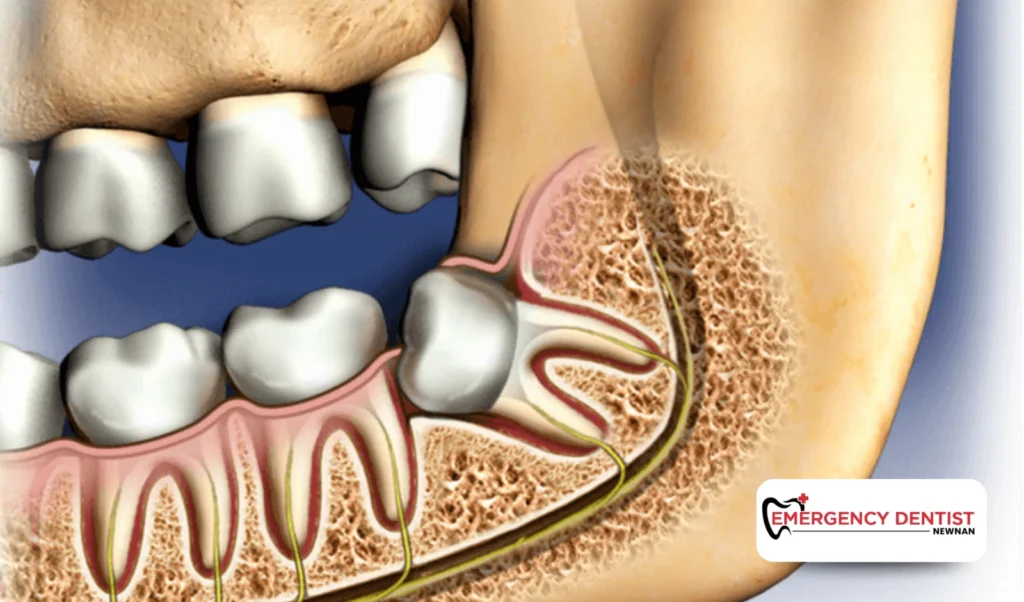

A surgical extraction is required when the tooth is partially erupted, broken, or beneath the gums. This commonly applies to an impacted wisdom tooth.

A surgical extraction may involve:

• Lifting gum tissue

• Removing small sections of bone

• Dividing the tooth into smaller pieces

Since this is a more advanced dental procedure, wisdom teeth removal cost is usually higher than a simple extraction.